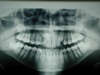

Les radios avant traitement